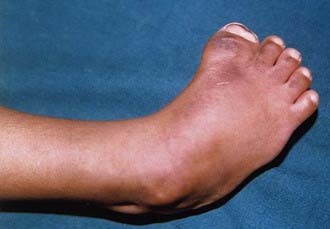

Congenital vertical talus has also been described as a rocker-bottom foot (Fig. 666-3) or a Persian slipper foot. The plantar surface of the foot is convex, and the talar head is prominent along the medial border of the midfoot. The fore part of the foot is dorsiflexed (dorsally dislocated on the hindfoot) and abducted relative to the hindfoot, and the hindfoot is in equinus and valgus. There is an associated contracture of the anterolateral (tibialis anterior, toe extensors) and the posterior (Achilles tendon, peroneals) soft tissues. The deformity is typically rigid. A thorough physical examination is required to identify any coexisting neurologic and/or musculoskeletal abnormalities.

image

Figure 666-3 Rocker-bottom foot in congenital vertical talus.